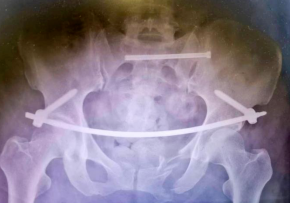

术中,先用骨盆牵引床,在C臂机监视下牵引左下肢,复位左侧骶骼关节后,骨科手术机器人通过专用C型臂透视下取得手术部位的图像,在电脑上分别规划好最佳置钉路径,机械臂随动运行调整到最佳角度,引导医生置入骶髂螺钉和INFIX螺钉,连接弯棒完成骨盆前环固定,透视各个角度见骨折复位及固定满意,无螺钉进入骶管及关节腔,切口予以全层缝合,手术顺利,术中出血仅20ml。

术中骶髂螺钉和INFIX内固定

手术通过骨盆耻骨上切口向内穿刺,将长杆从切口置入骨盆内,将其穿过断裂处。通过双侧梭形头螺钉固定,将腰部和骨盆稳定连接。INFIX微创手术主要具有手术时间短、创伤小、出血少、固定牢靠等优点,与传统微创手术相比,更适合老年人骨盆骨折康复期的治疗。